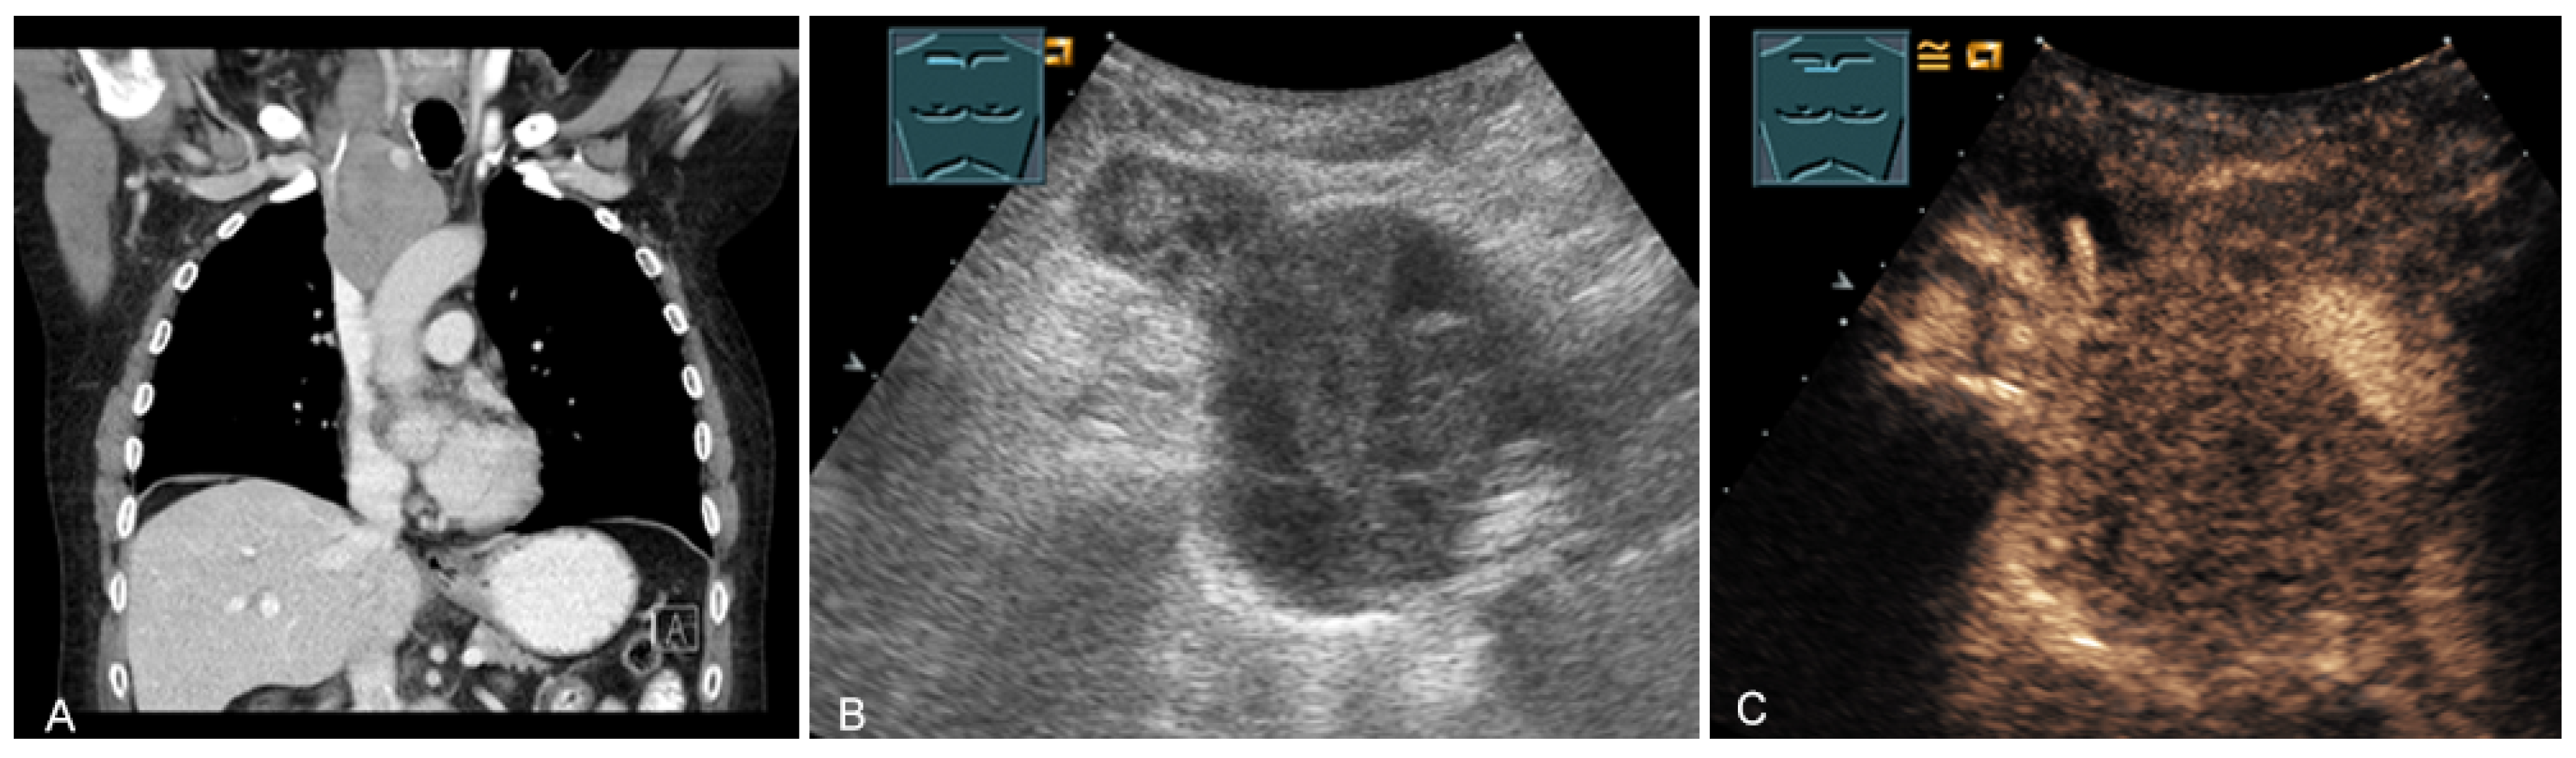

Figure 15.

An echogenic mediastinal mass as an incidental finding on CT (provided by Prof. Dr. Andreas H. Mahnken, Marburg, Germany) (A), B-mode US (B), and CEUS (C), evaluated by imaging as a retrosternal located thyroid gland.